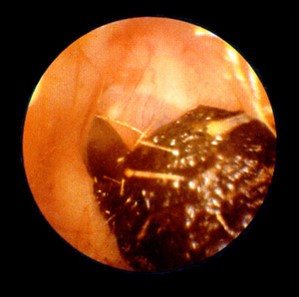

Tök cuki volt, ugye? Most pedig íme, egy kis fülzsír.

Még mindig nem hánysz? Semmi gond, fogsz. A fülzsírt ne akard te magad kipiszkálni, inkább menj fülészetre, ott kimossák. Szar érzés, mert a fül- orr- gégészek szadisták, eredetileg a vágóhídon akartak dolgozni, de mosás után mintha újjászülettél volna.